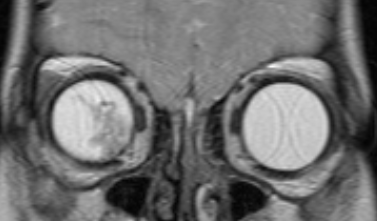

![Визуализация ретинобластомы с помощью МРТ. Фронтальное изображение орбит. Клиническая группа D]()

Рис. 4. Визуализация ретинобластомы с помощью МРТ. Фронтальное изображение орбит. Клиническая группа D